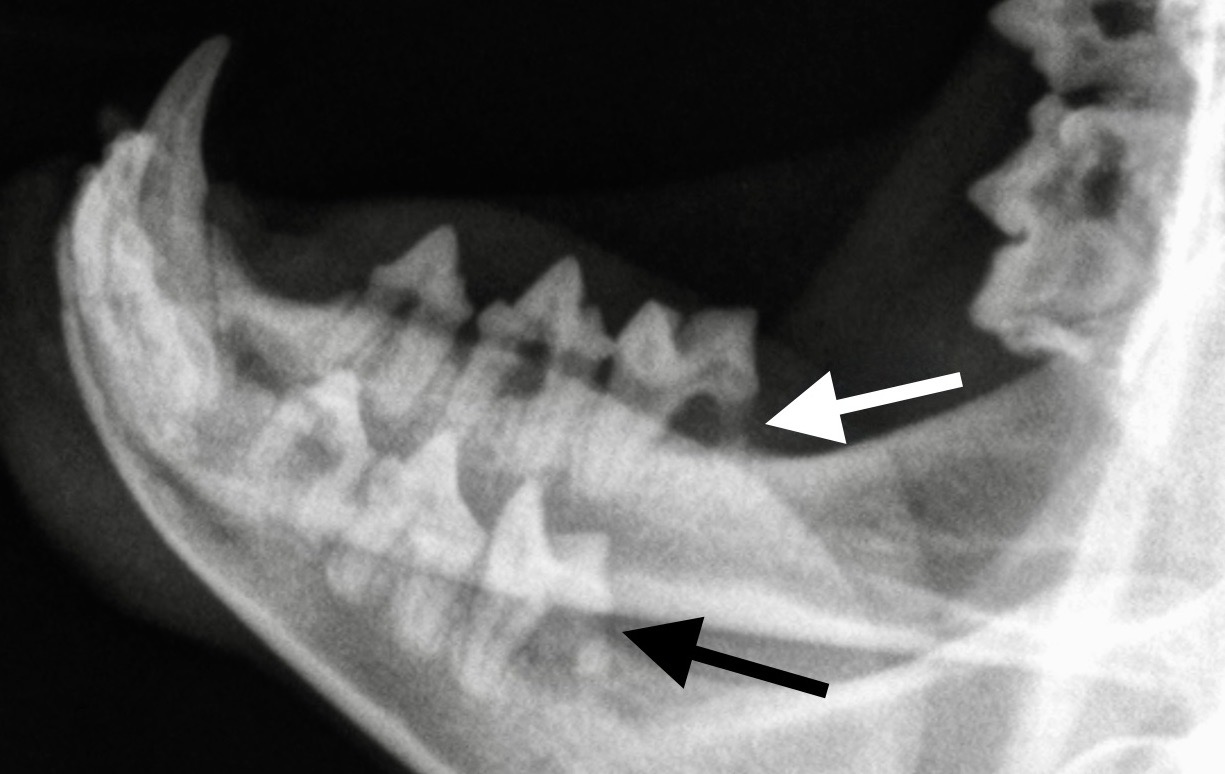

La photo de gauche montre des lésions de résorption du collet, sur une prémolaire et une molaire inférieures d’un chat en cours de détartrage : les flèches montrent la distance importante qui sépare la gencive (qui saigne au moindre contact), de la couronne de la dent : cette dernière est lysée, notamment sur la partie la plus caudale de la molaire. Photo de droite : et voilà ce que ça donne à la radio : la racine caudale des deux molaires inférieures a été rongée au point de quasiment disparaître (flèches).

On va le voir juste après, la mesure la plus importante dans le traitement de la GSCF, ce sont les extractions dentaires – et souvent, ce sont presque toutes les dents que l’on retire. Et on a vu plus haut qu’un débris de racine qui traîne alors que le reste de la dent est parti, peut suffire à entretenir l’inflammation de la bouche. Il est donc intéressant de pratiquer des radiographies dentaires avant de s’attaquer aux extractions, afin de débusquer les racines enfouies qui pourraient passer inaperçues après un simple examen externe. (Photo ci-contre : la racine postérieure de ces deux molaires ne va pas tarder à casser, avec le risque que l’extrémité arrive à se faire oublier, bien cachée au fond de son alvéole !)